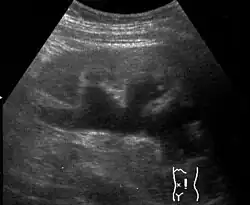

Renal ultrasonography of hydronephrosis[16]